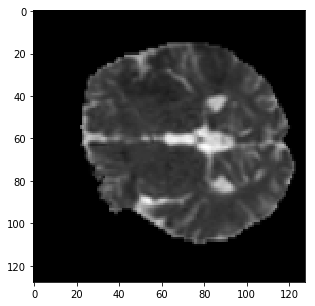

The qualitative results are shown in Fig. 2. Addition of LS and BD losses while training the network significantly improves the boundary delineation in the results. This improvement is more drastic when the network is adversarially trained as seen in the results of the proposed method as compared to BL7.

[TMax]

\subfigure[TTP]

\subfigure[DWI]

\subfigure[GT]

[BL3]

\subfigure[BL4]

\subfigure[BL7]

\subfigure[Proposed]